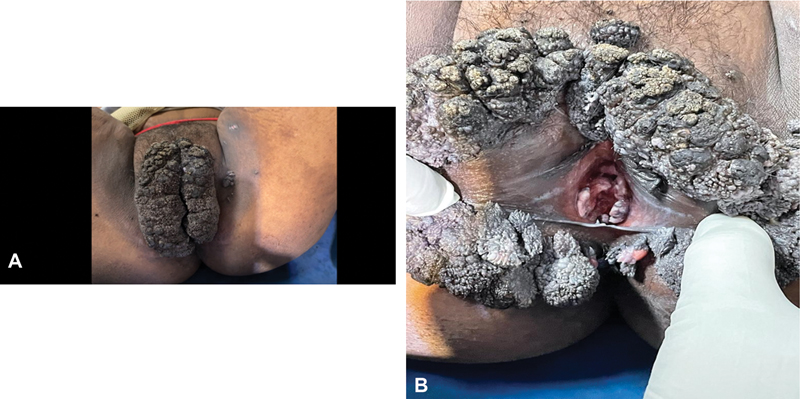

An 18-year-old girl presented in the outpatient department with warty growth in her vulval region for 1 year. The growth has been gradually increasing in size over the last 12 months. She was first evaluated in a peripheral hospital, where a biopsy of the mass was done and reported as verrucous hyperplasia in histopathology report. She was from a family with a low socioeconomic background. Upon clinical examination, she was found to be moderately built with a body mass index of 20.8, Eastern Cooperative Oncology Group 0, and mild pallor. Other systems were normal. No signs of any discomfort, mass, or free fluid were present in the abdomen. A large friable growth that involved both of her labia majora and extended anteriorly to the mons pubis and posteriorly to the perianal region was detected during a local examination of her genitalia. ([Fig. 1A]). On the thighs, perianal region, and labia minora, there were a few satellite lesions ([Fig. 1B]). The clitoris, urethra, and external anal sphincter were unaffected. The patient's HPV deoxyribonucleic acid (DNA) test, human immunodeficiency virus (HIV), hepatitis B surface antigen, and screening for sexually transmitted diseases (STDs) were negative. She denied any sexual contact in the past. The patient had not been vaccinated for HPV.

Fig 1: (A, B) Cauliflower-like growth that involved both of her labia majora and extended anteriorly to the mons pubis and posteriorly to the perianal region.

Fig 1: (A, B) Cauliflower-like growth that involved both of her labia majora and extended anteriorly to the mons pubis and posteriorly to the perianal region.